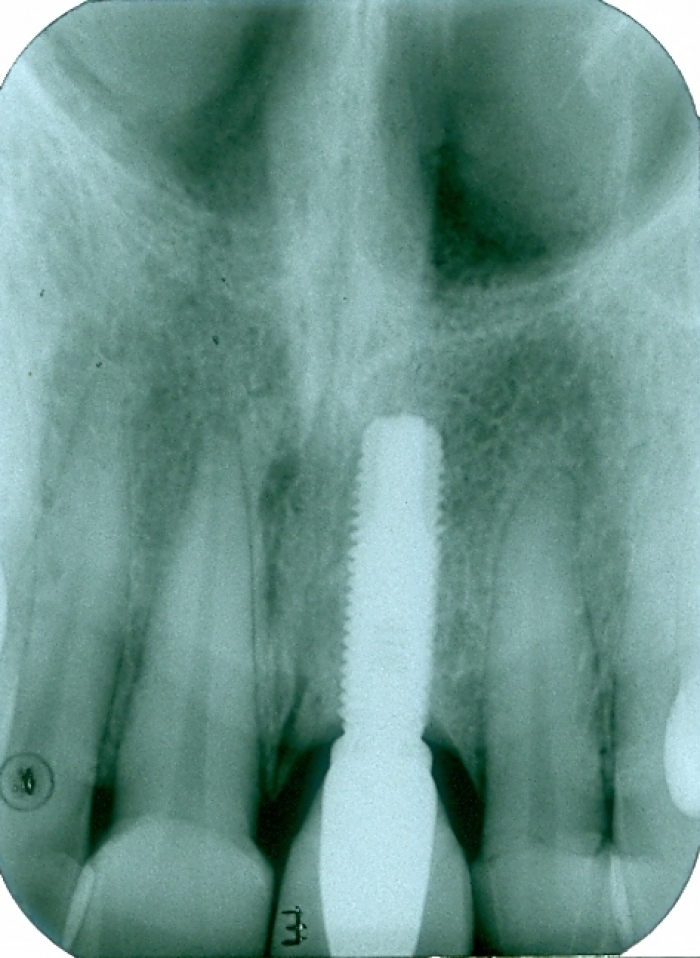

Raio X inicial